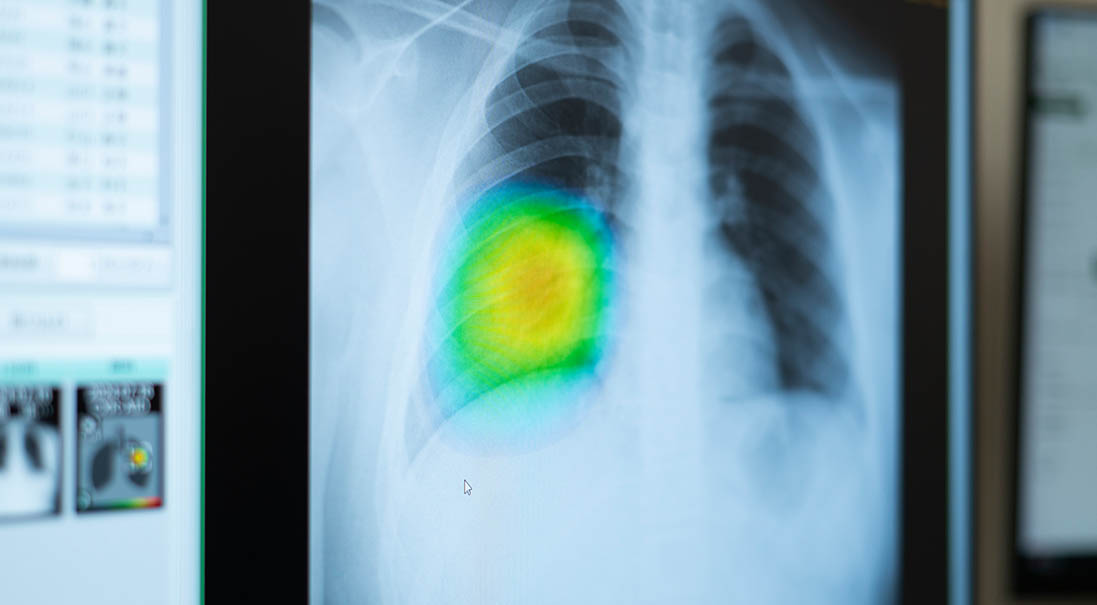

当院ではFUJIFILM社のCXR-AID搭載のレントゲン機器を用いてAI技術を活用した検査を行っています。

※CXR-AID

胸部X線画像の自動解析を行います。病変の存在が疑われる領域を検出・マーキングし、見落し防止を支援します。